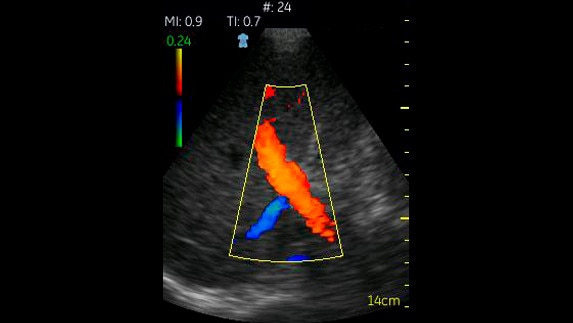

Vascular